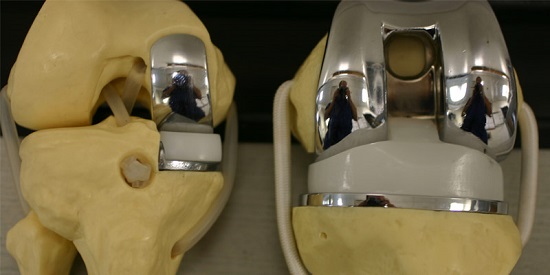

انواع مفاصل الركبة الصناعية

تختلف مفاصل الركبه الصناعيه في تصميمها وأنواعها حسب احتياج المريض وحالته الهدف عموما من مفاصل الركبه الصناعيه هو استبدال سطح الركبه المتاكل باخر صناعي أملس يمنع الألام الناتجه عن خشونه الركبه ويجعل حركه الركبه مرنه ليتمكن المريض من المشي بسهوله مره اخري.

ببساطه، المفصل مكون جزئين مصنوعين من سبيكه معدنيه تتحمل الضغوط والأحمال لمده سنوات طويله وتثبت القطعتين علي الأجزاء المساهمه في مفصل الركبه من أسفل عظمه الفخذ وأعلي عظمه القصبه وتثبت بين السطحين المعدنيين قطعه مصنوعه من اللدائن البلاستيك (بولي اثيلين) وتسمح هذه القطعه بالحركه بنعومه ويسر.

هناك انواع مفصل الركبة واسعارها منها المفاصل ذات السطح غير المتحرك وأخري ذات سطح متحرك تسمح بحركه دوران القصبه للداخل والخارج مما يتيح حركه أكثر انسيابيه ويطيل عمر القطعه البلاستيكيه في المفصل.

كما يوجد انواع مفاصل للركبه ذات مفصل محوري في المنتصف يستخدم في الحالات التي تعاني من عدم ثبات واضح بسبب مشاكل بالاربطه المحيطه للركبه.

كما يوجد نوع من مفاصل الركبه يكون نصف مفصل فقط ويستخدم في حالات تاكل جهه من مفصل الركبه دون الاخري.

كل مفصل ركبة بديل يتألف من ثلاث أجزاء: جزء خاص بالفخذ وآخر خاص بالساق وجزء قائم على اللدائن يتمركز على الظنبوب.

تركيب الركبة الصناعية

فى هذه الجراحة بعد تخدير المريض, يتم إزالة الأسطح المتهالكة من عظام الفخذ والقصبة (و الصابونه فى بعض الحالات) وإستبدلها بأجزاء صناعية بحيث يختفي الألم الناتج عن إحتكاك العظام ببعضها ويزداد مدى الحركة فى الركبة وتستغرق الجراحة عادة ما بين 60 – 90 دقيقة على حسب صعوبة الحالة والنوع الذي يعتمد علي سعر الركبة الصناعي ومن مزايا هذه الجراحة أن أي أعوجاج (تقوس) بالساق يتم إصلاحه من خلال الجراحة نفسها ويستطيع المريض المشي على رجله فى اليوم التالي للجراحة مباشرة بمساعدة عكازات. ويمكن إجراء هذه الجراحة من خلال جرح صغير كما أن هناك تقنيات حديثة مثل المفصل ثلاثي الأبعاد تستخدم فى بعض الحالات واستخدام الروبوت فى إجراء الجراحة.

ويتكون مفصل الركبة الصناعي من جزء معدني يغطي سطح عظمة الفخذ وآخر يغطي القصبة وبينهما مادة بلاستيكية بيضاء ذات قوة عالية لمنع الأحتكاك بينهم وفى حالات قليلة قد يتم تركيب جزء بلاستيكي يغطي سطح عظمة الصابونة (الردفة) ويتم تثبيت هذه الأجزاء فى العظام عادة بواسطة مادة تسمى الأسمنت العظمي وهناك انواع من مفاصل الركبة الصناعية يتم تركيبها بدون أسمنت طبي ولكن إستخدامها غير شائع نظرا لإرتفاع تكلفنها وعدم ثبوت تميزها عن المفاصل الأسمنتيه.